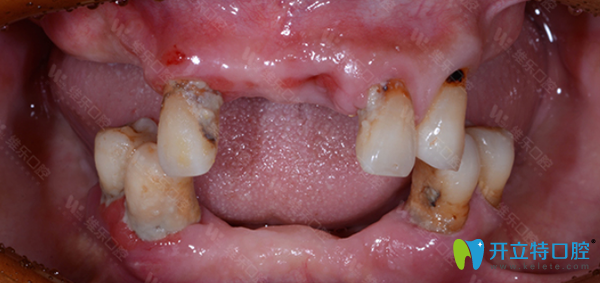

口腔問題:牙齒脫落,牙槽骨脆弱,沒有牙營養(yǎng)吸收低,整個人渾身無力。

種牙前,王大爺飽受缺牙帶來的種種折磨。經(jīng)翟建博主任仔細檢查后,建議采用數(shù)字化即刻負重種植牙技術(shù),來修復(fù)王大爺缺失的牙齒。

看看王大爺在維樂口腔種牙前后的效果對比照片: